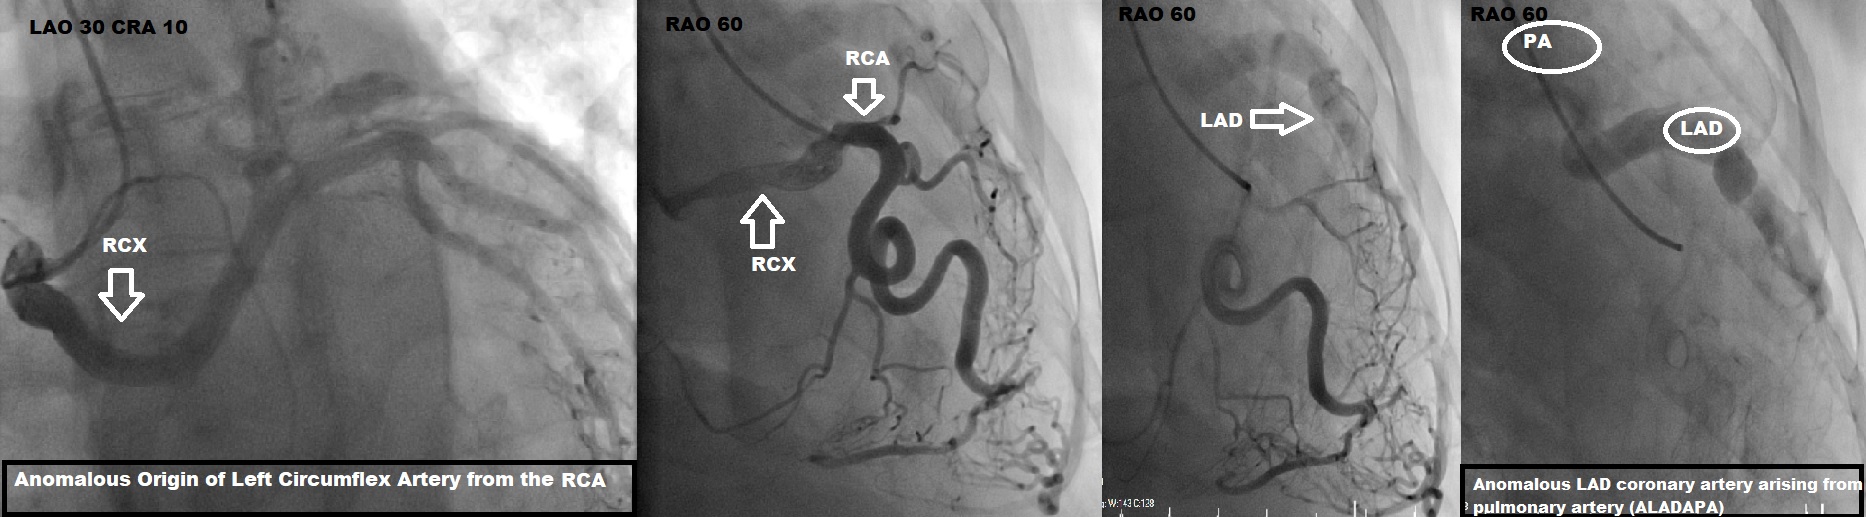

We report a case of a 52-year-old male who presented with progressive exertional dyspnea and clinical signs of heart failure. Electrocardiography showed no typical signs of ischemia. Laboratory findings showed significantly elevated N-terminal pro-B-type natriuretic peptide. Transthoracic echocardiography revealed severely impaired left ventricular ejection fraction. Coronary angiography was performed and showed a complex double coronary anomaly with an anomalous origin of the left coronary artery from the pulmonary artery with extensive collateralization from the right coronary artery supplying the left coronary system. Additionally, an anomalous origin of the circumflex artery from the right coronary artery with benign course, which is one of the most common coronary artery anomalies, was found. The diagnosis was subsequently confirmed by computed tomographic (CT) coronary angiogram with 3D reconstruction, which showed ectatic RCA arising from the right coronary sinus and the left descending artery arising from the pulmonary artery. Cardiac Magnetic Resonance (MR) demonstrated thinning of anterolateral wall of the left ventricle with sub endocardial delayed gadolinium enhancement.